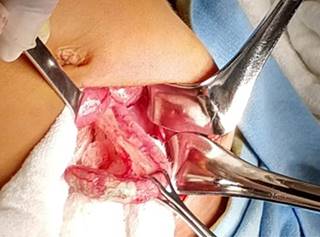

Dentro de sus exámenes de laboratorio encontramos a un paciente sin leucocitosis, sin embargo, con neutrofilia marcada (leucocitos 10.0 WBC 79.3), y el examen general de orina se presentó sin alteraciones. Integramos un síndrome de abdomen agudo, con diagnóstico probable de apendicitis aguda complicada, por lo que se decidió realizar una laparotomía exploradora en línea media infraumbilical, y se obtuvo como hallazgo transoperatorio trasposición de vísceras abdominales y apendicitis complicada con absceso pélvico (Figuras 1 y 2).